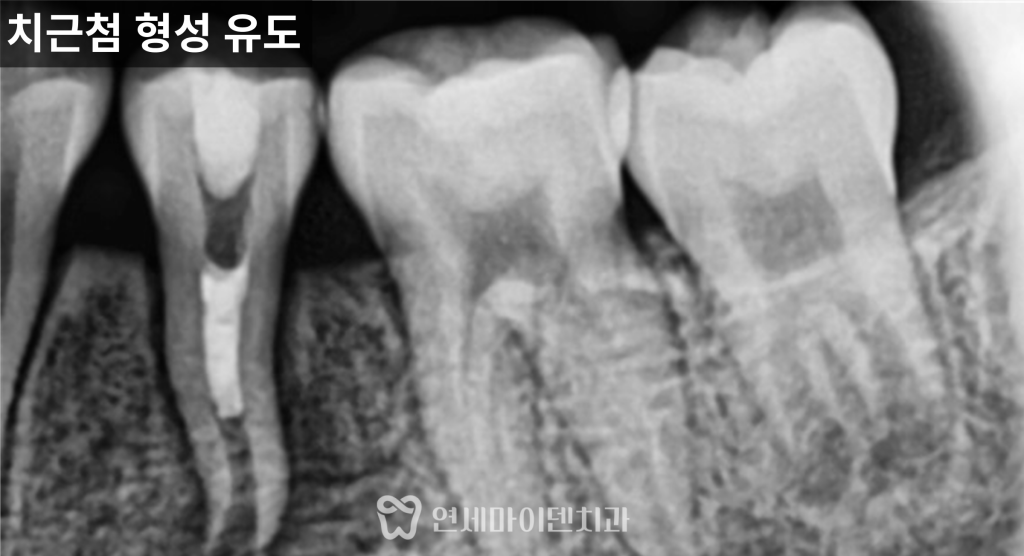

그래서 이번 케이스에서는

치근단 형성술을 선택했습니다.

이 치료는 뿌리 끝의 살아있는 조직을 최대한 보존해

시간이 지나면서 뿌리 길이와 두께가

자연스럽게 성장하도록 유도하는 방법입니다.

치아 내부 감염을 제거하기 위해

신경치료를 진행했지만,

뿌리 끝까지 완전히 밀폐하는 방식이 아니라

성장을 고려해 중간 단계까지 치료를 진행했습니다.